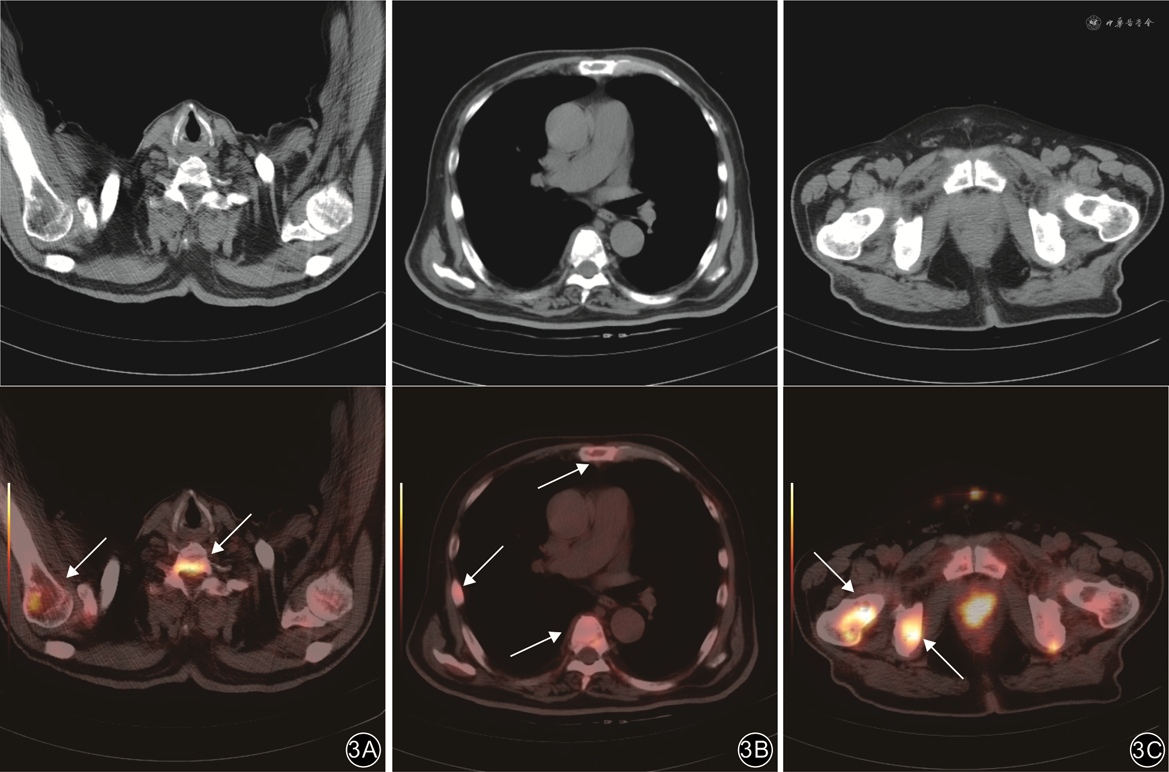

肺癌骨转移和前列腺癌骨转移病灶以高代谢为主,SUVmax较高,分别为5.70~29.10(15.51±5.60)和4.30~15.10(9.41±3.47)。在42例肺癌骨转移病例中,有41例(97.6%)显示SUVmax≥6.0;而在30例前列腺癌骨转移病例中,有24例(80.0%)显示SUVmax≥6.0。MM病灶以弥漫性轻中度代谢为主,SUVmax较低,为0.80~12.00(5.39±2.84)。在36例MM病灶中,有12例(33.3%)显示SUVmax≥6.0。3组间SUVmax比较差异有统计学意义(F=54.66,P<0.001),组间两两比较差异均有统计学意义(P值均<0.05)。

注:上排为CT图像;下排为对应位置的正电子发射体层摄影(PET)/CT融合图像